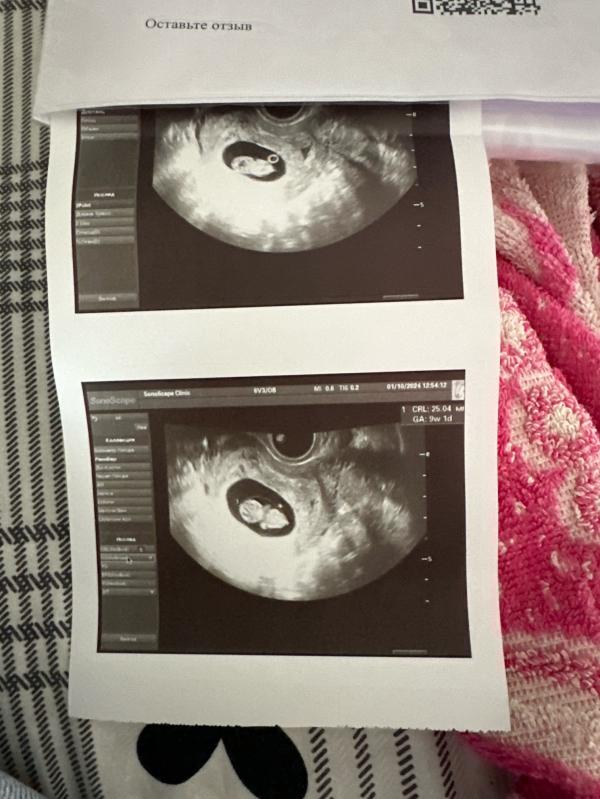

Мы растем

РХГ к сожалению которая была еще на первом узи Так и осталась И как я поняла добавилась новая 😞

Но не смотря на это малыш растет как надо

Прописали папаверин на пять дней